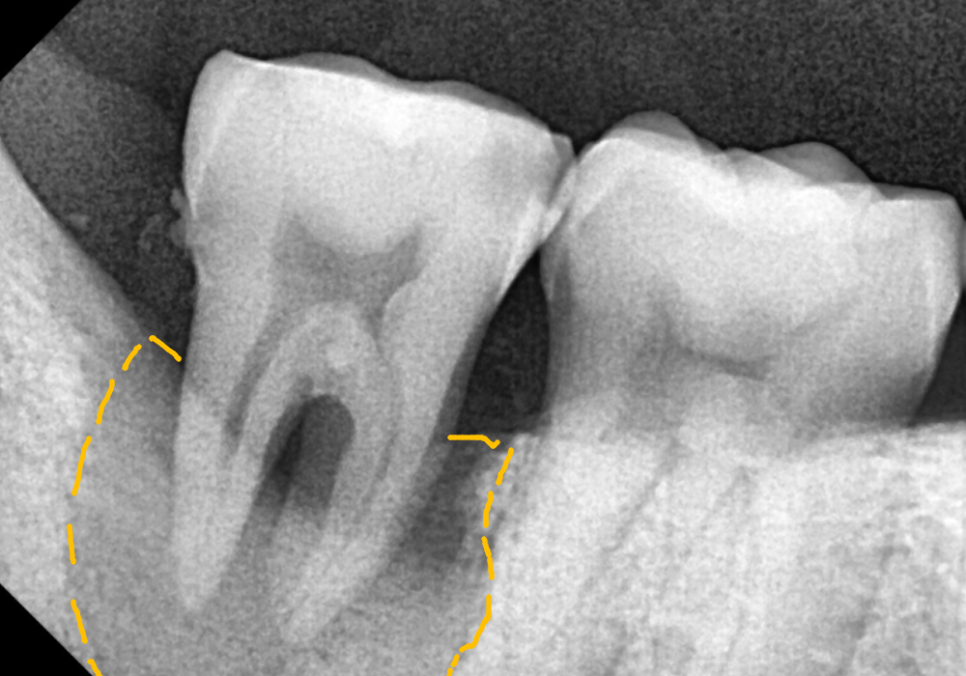

아래쪽(#47): 신경관 인접성

오른쪽 아래 역시 CT 상에서 확인하니

뼈가 신경관 바로 근처까지 녹아 있네요.

임플란트를 지탱해 줄 뼈가

거의 없는 상태였기에,

이럴 경우, 뼈이식을 진행하여

임플란트가 안정적으로

식립될 수 있는 환경을 먼저 만들어야 합니다.